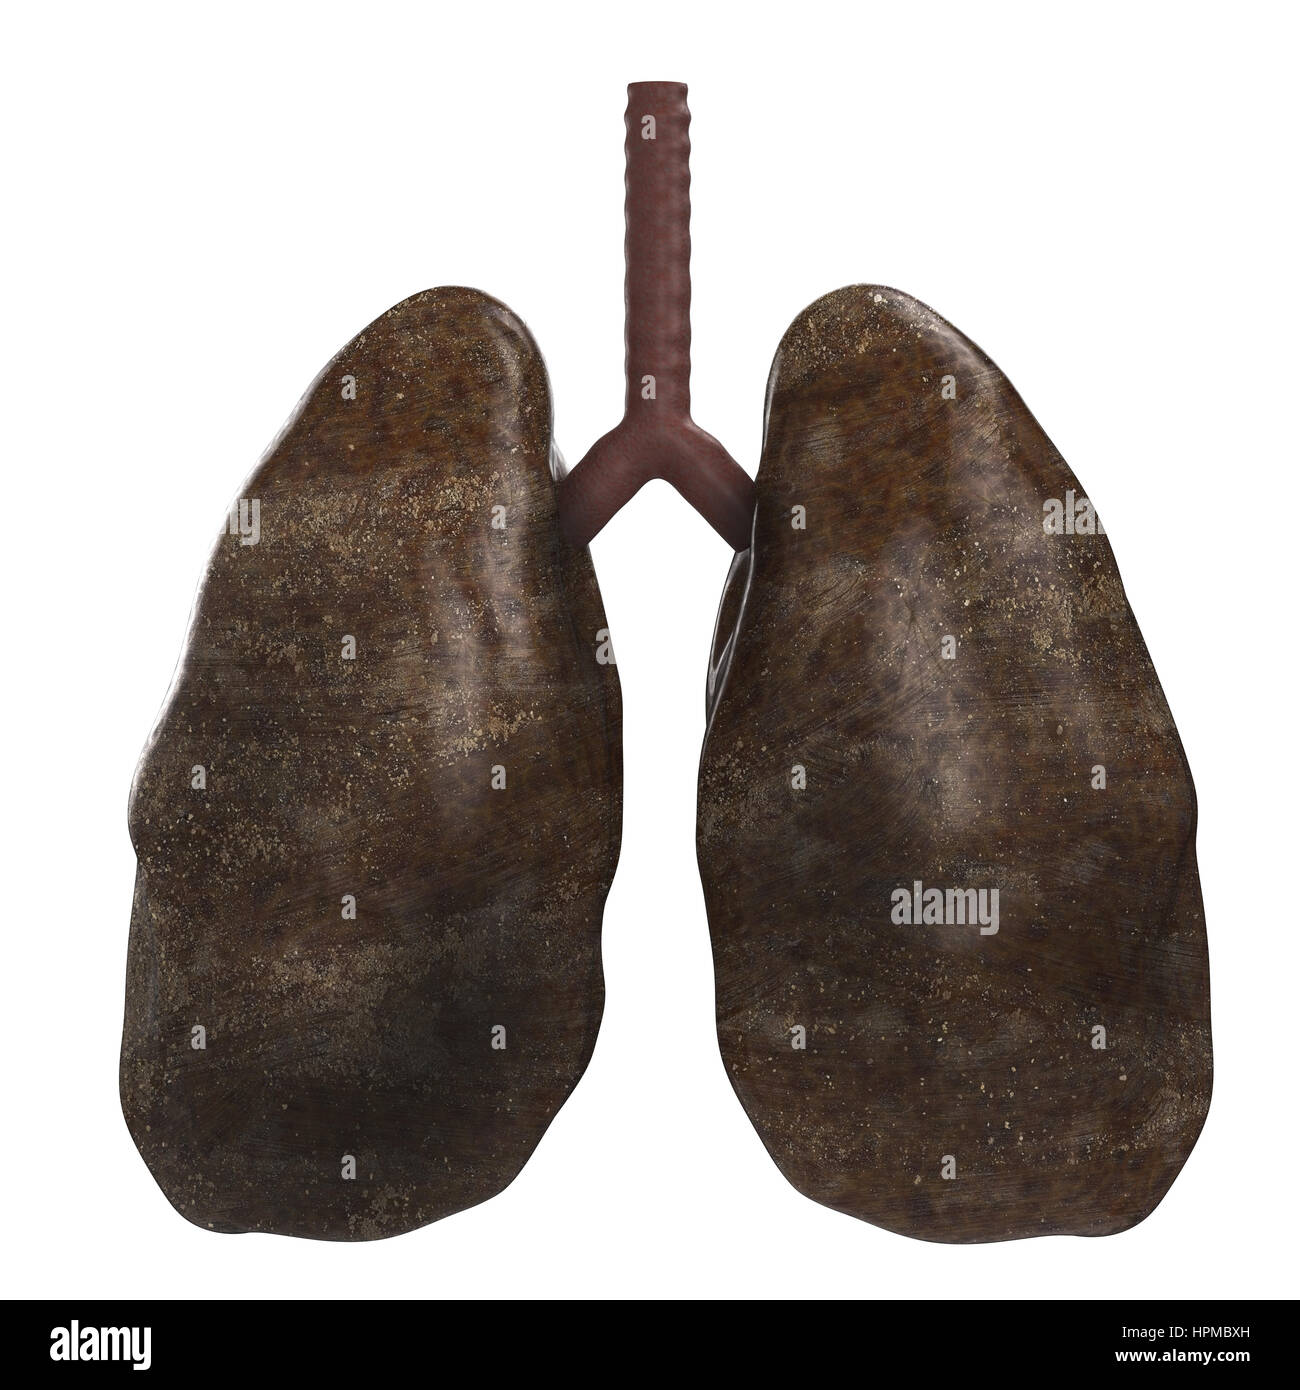

Le rendu 3d des poumons ou des poumons malsains